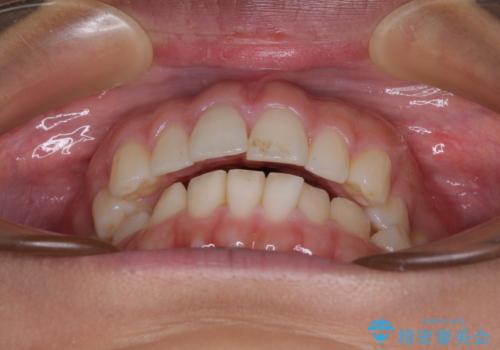

【モニター】突出した前歯 補助装置を併用したインビザライン矯正

- 上下前歯が非接触となり、前方に突出していることを気にして来院された患者様です。

咬合力が強く、全体的に歯がすり減っているため、インビザライン単独での上顎歯列移動は困難と判断し、補助装置により上顎歯列を後方移動させ、その後インビザラインにて仕上げていくこととしました。

補助装置なしでも改善できる可能性はありましたが、補助装置で確実性を上げ、短期間できっちりと仕上げることができました。